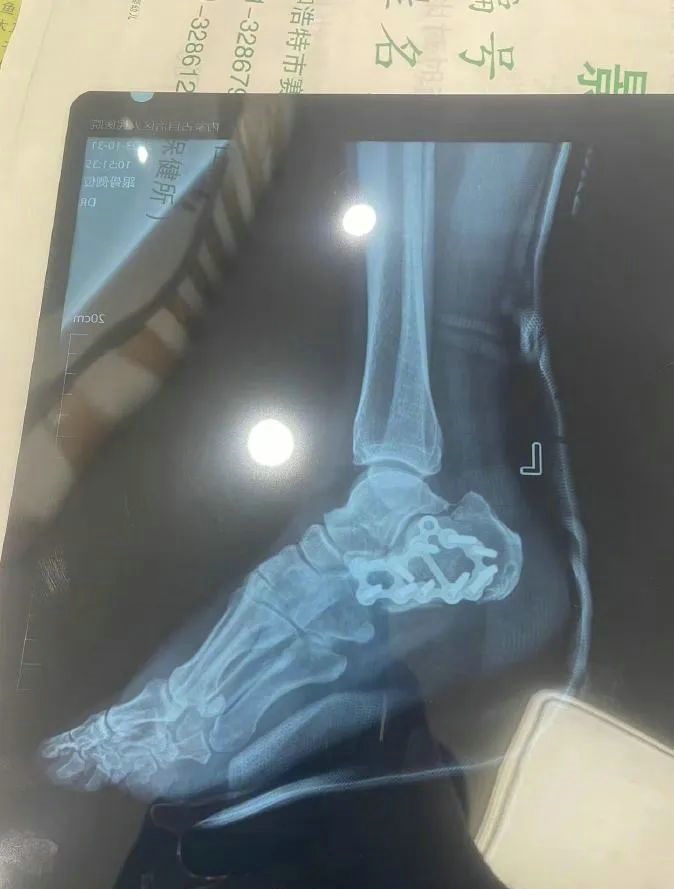

“那時(shí)候我剛工作了兩天,在第三天10月22日下午施工過(guò)程中從三層高的鐵架上摔了下來(lái),導(dǎo)致30厘米左右的鋼筋刺穿我的右側(cè)臀部,左腳跟也粉碎性骨折,被送往內(nèi)蒙古自治區(qū)人民醫(yī)院救治,當(dāng)晚做了手術(shù)取出刺在右臀部的鋼筋,10月30日又進(jìn)行了左腳粉碎性骨折手術(shù)?!崩紫壬嬖V記者。

2.jpg